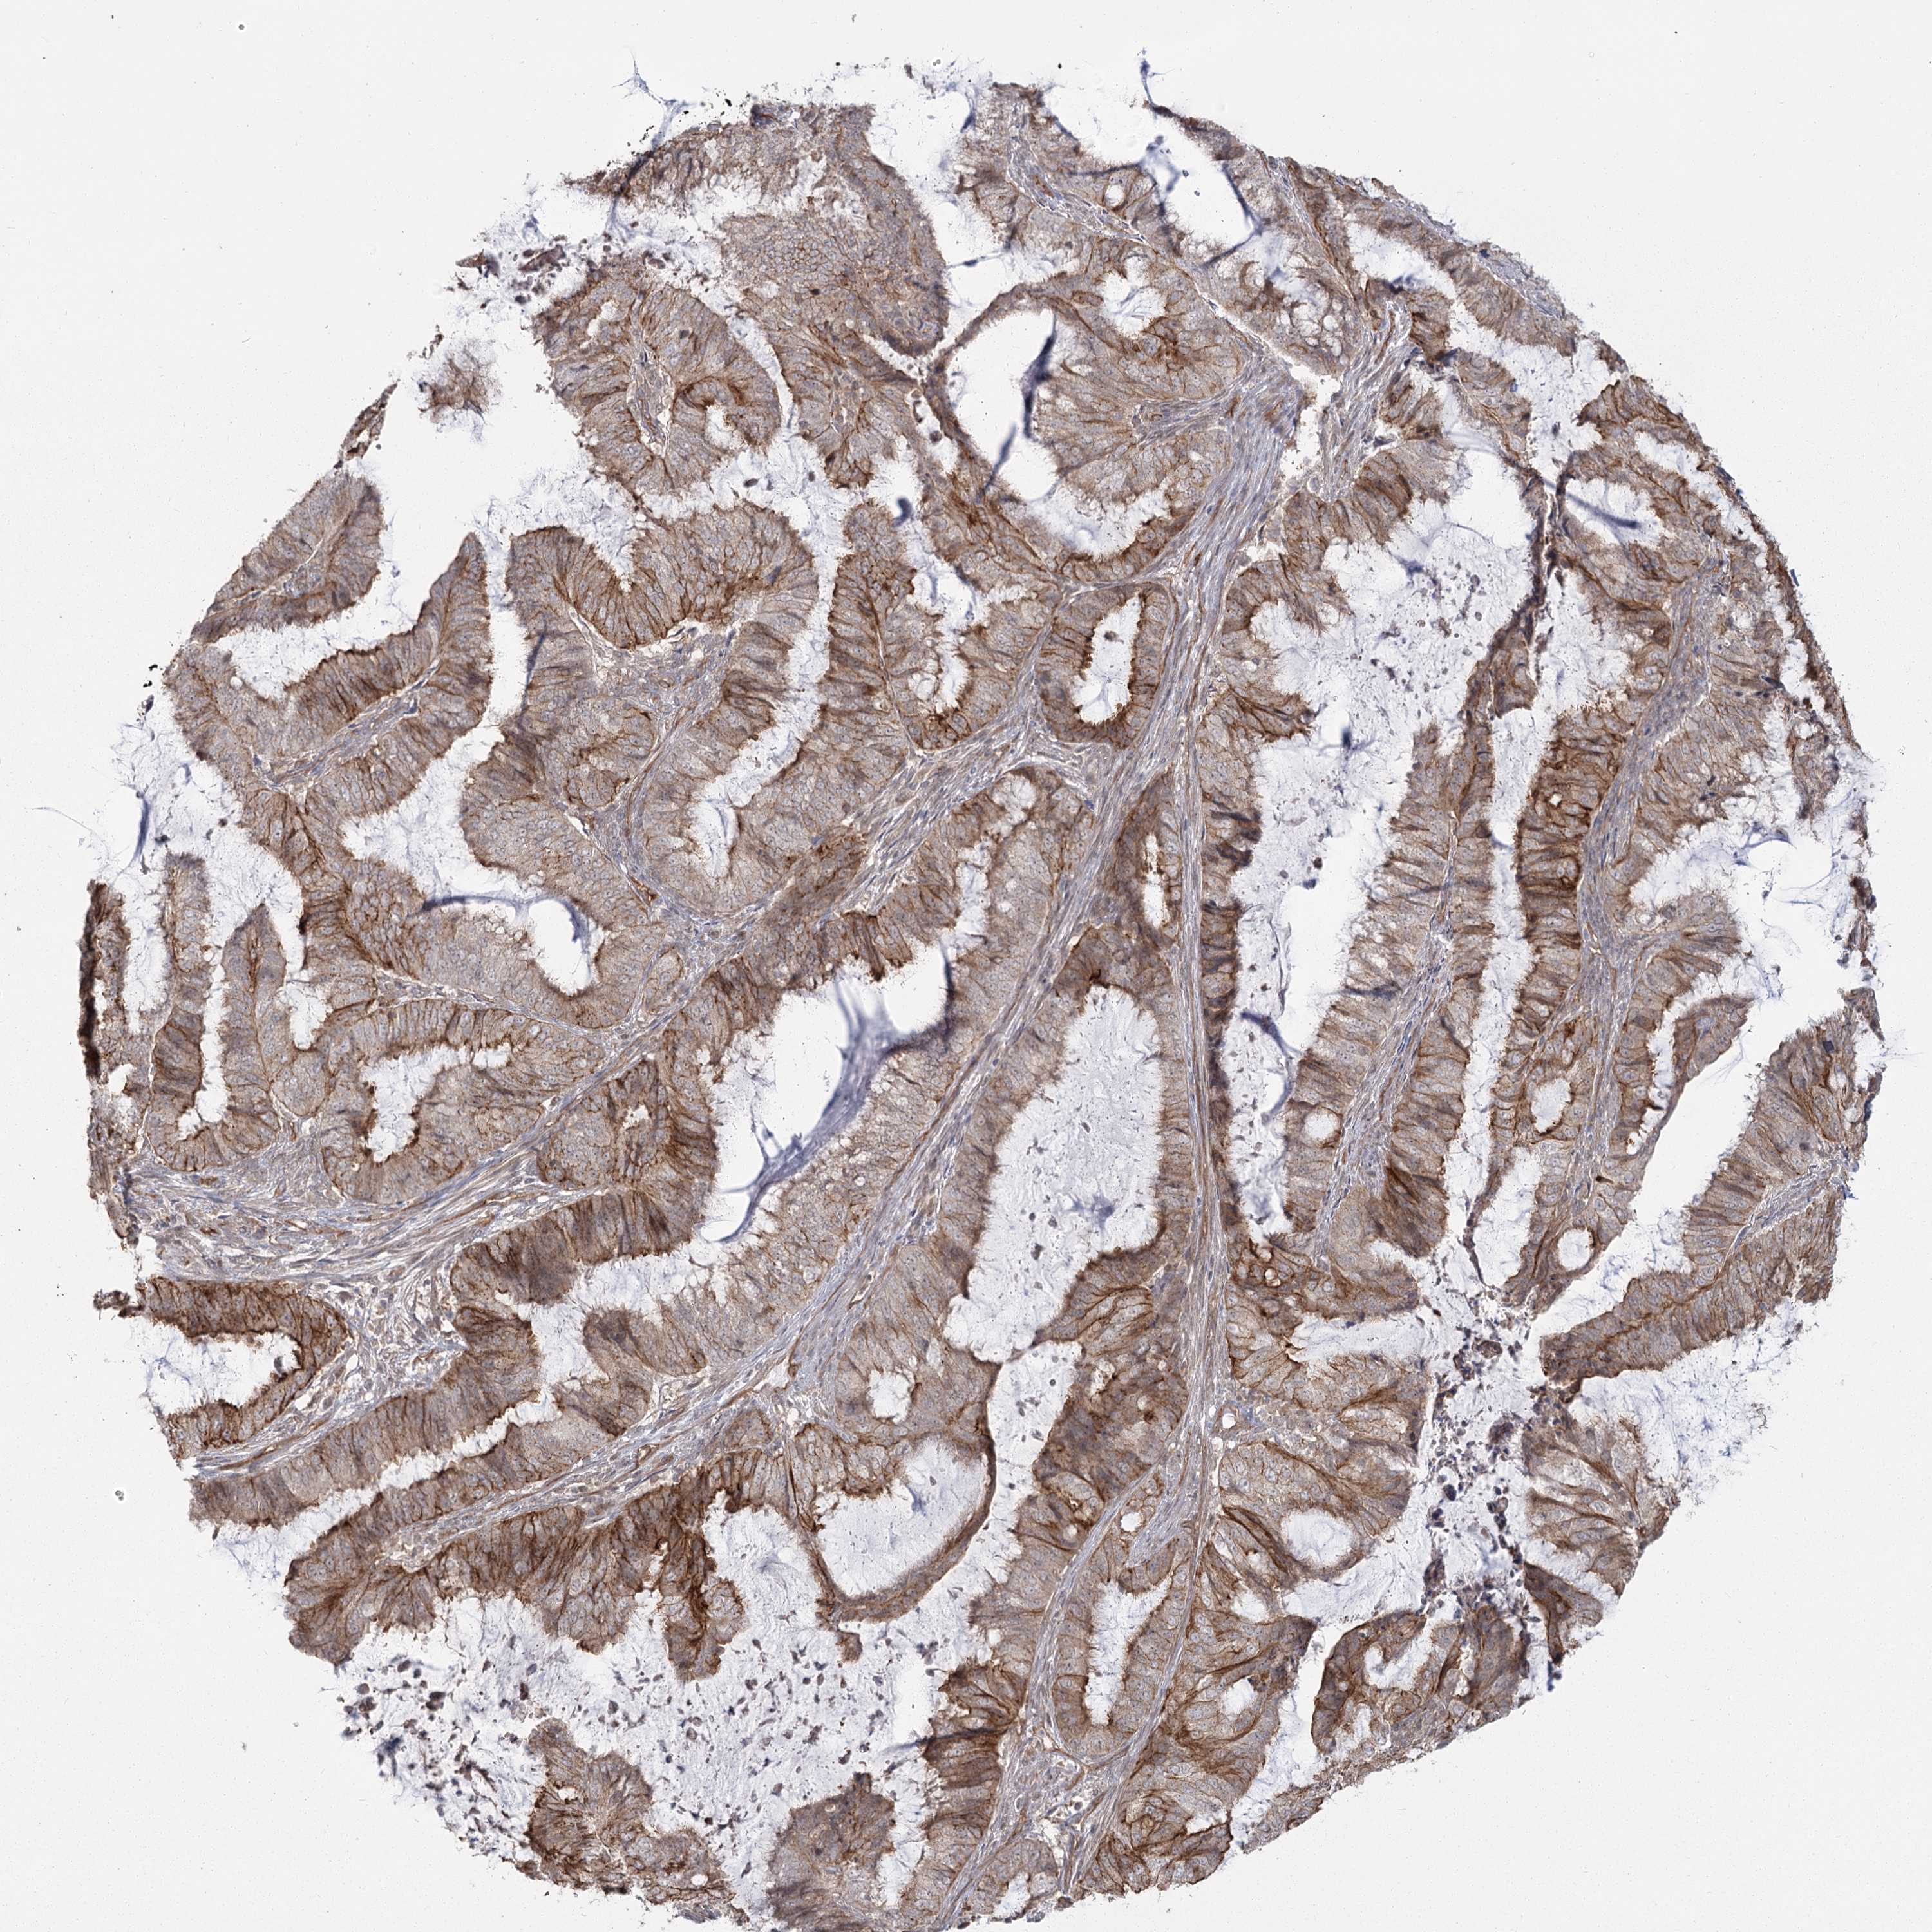

ENDOMETRIAL CANCER - Protein expressioni

A mouse-over function shows sample information and annotation data. Click on an image to view it in a full screen mode. Samples can be filtered based on level of antibody staining by selecting one or several of the following categories: high, medium, low and not detected. The assay and annotation is described here.

Note that samples used for immunohistochemistry by the Human Protein Atlas do not correspond to samples in the TCGA dataset.

Antibody stainingi

Antibody staining in the annotated cell types in the current human tissue is reported as not detected, low, medium, or high, based on conventional immunohistochemistry profiling in selected tissues. This score is based on the combination of the staining intensity and fraction of stained cells.

Each image is clickable and will lead to virtual microscopy that enables deeper exploration of all samples and also displays staining intensity scores, fraction scores and subcellular localization as well as patient and tissue information for each sample.

Antibody HPA036194

Staining

High

Medium

Low

Not detected

Intensity

Strong

Moderate

Weak

Negative

Quantity

>75%

75%-25%

<25%

None

Location

Nuclear

Cytoplasmic/membranous

Cytoplasmic/membranous,nuclear

Adenocarcinoma, NOS

Adenocarcinoma, metastatic, NOS